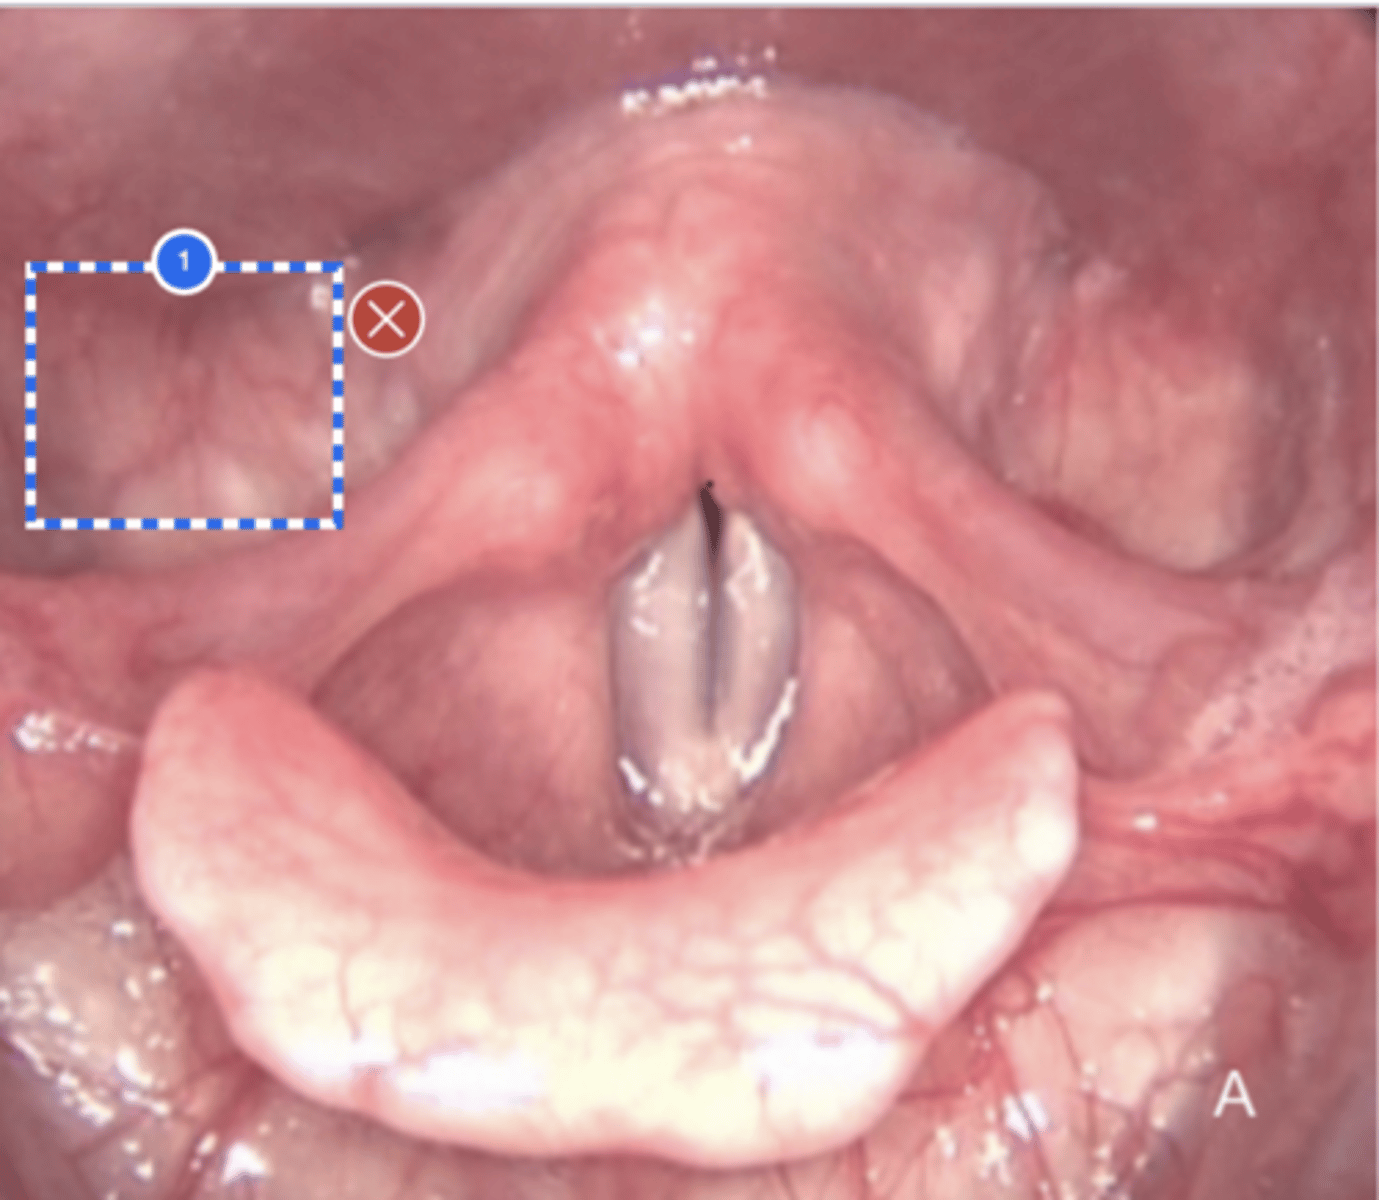

Label Laryngeal surface of epiglottis (superior view)

Label (Right) Lateral pharyngeal wall (superior view)

Label Base of tongue (superior view)

Label left vallecula (superior view)

Label Posterior Pharyngeal Wall